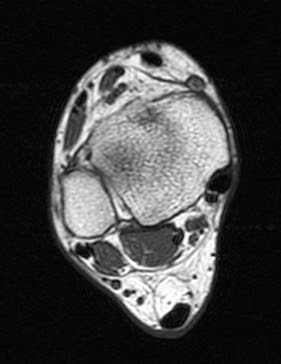

Foot Muscles Mri - foot mri t1 coronal image / These muscles begin and attach within the skeleton of the foot, have complex anatomical and topographical and functional relationships with.

Related posts of foot muscle anatomy mri. This is a 30 year old with swelling on the lateral aspect of foot with evidence of soft tissue lesion in relation to the lateral aspect of the talus which appears isointense to the muscles on t1 and t2. Posted by radiologyer at 8:12 am. Top suggestions for foot muscle anatomy mri. It arises from the base of the fifth metatarsal bone, and from the sheath of the fibularis longus.

This is the first of two parts on the intrinsic muscles of the foot. Posted by radiologyer at 8:12 am. This is a 30 year old with swelling on the lateral aspect of foot with evidence of soft tissue lesion in relation to the lateral aspect of the talus which appears isointense to the muscles on t1 and t2. ► hip ► pelvis ► thigh ► knee ► lower extremity/shin ► ankle ► foot. Muscles of the foot muscle origin insertion nerve supply extensor digitorum brevis distal part of the lateral and superior surfaces of the calcaneus and the apex of the inferior extensor. ► shoulder ► elbow ► wrist ► finger ► thumb. Explore more like foot muscle anatomy mri. Related posts of foot muscle anatomy mri.